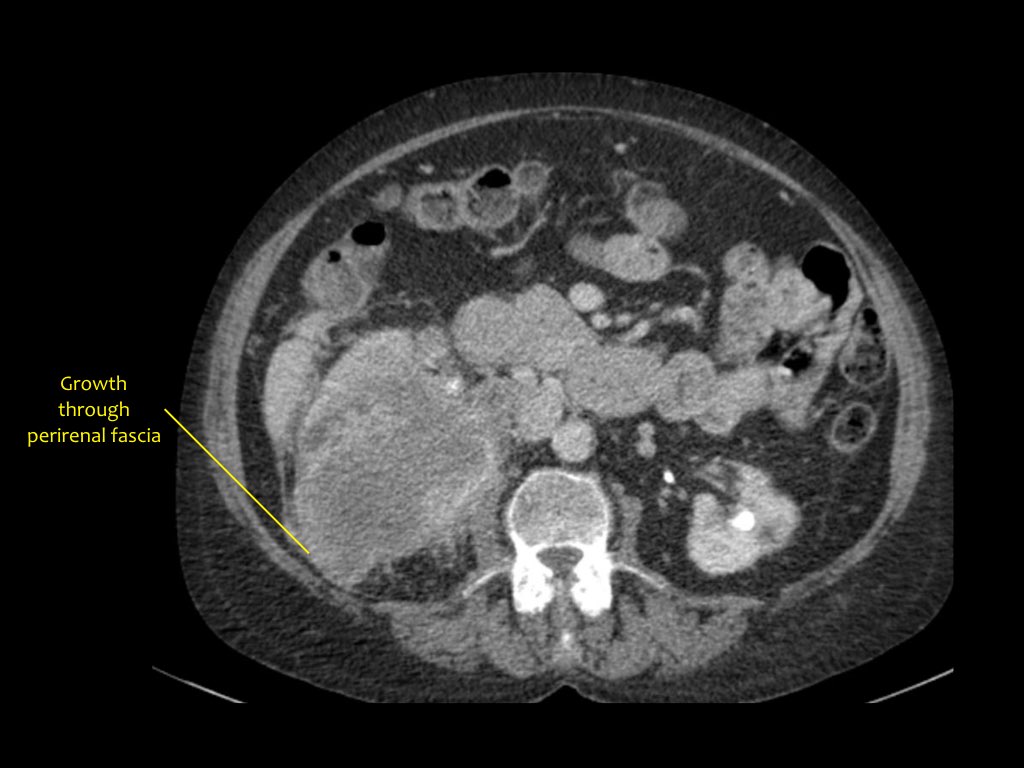

Phân giai đoạn RCC

RCC có thể xâm lấn mỡ quanh thận vượt qua cân thận và có thể lan vào tĩnh mạch thận, tĩnh mạch chủ dưới (IVC) hoặc tuyến thượng thận cùng bên.

Đối với phẫu thuật viên, điều quan trọng là cần biết có huyết khối u trong IVC hay không và liệu huyết khối có lan vào lồng ngực trên cơ hoành hay không (cần có phẫu thuật viên lồng ngực trong ca mổ).